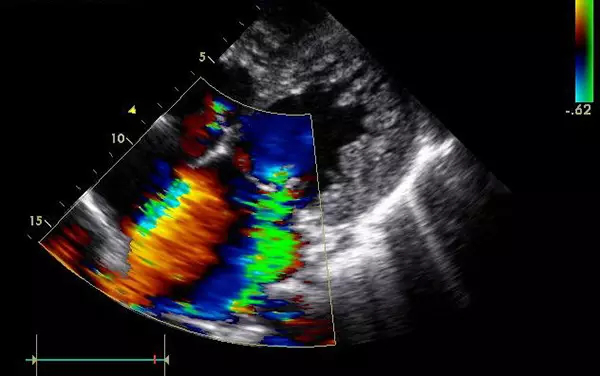

5、心臟——排除冠心病用CT,看心功能用超聲